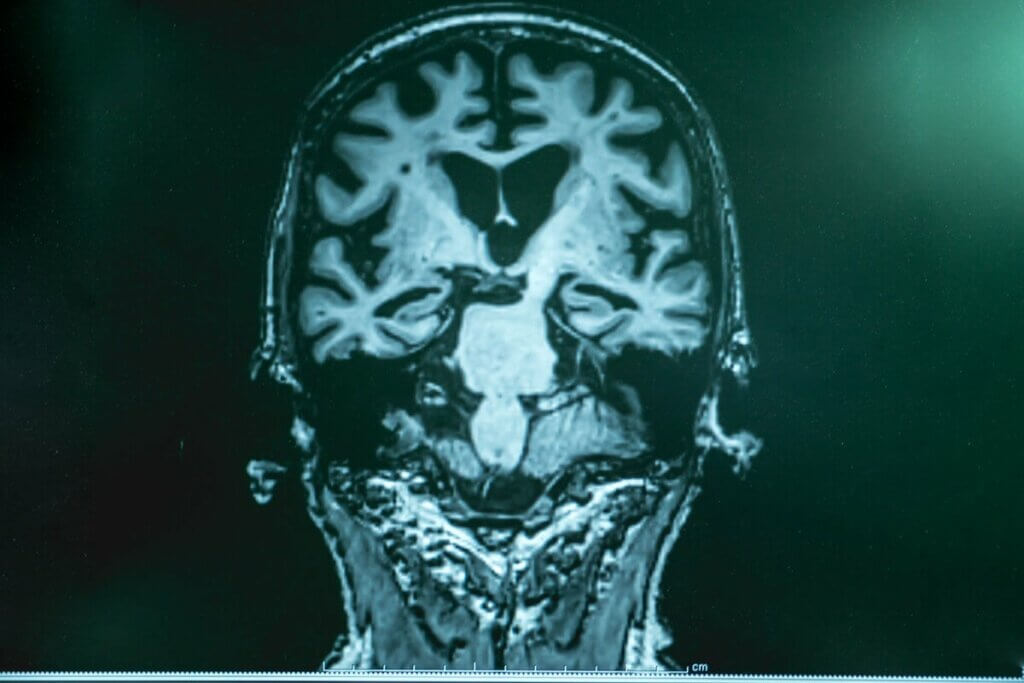

Como mencionamos no início, a origem do Alzheimer não é totalmente conhecida. Conhecemos apenas algumas alterações fisiopatológicas características da doença: os depósitos de proteína beta amiloide que acabam formando placas ao redor dos neurônios e os inutilizam, a formação de emaranhados neurofibrilares intracelulares e a presença de proteína tau fosforilada.

Como já foi estudado, a atividade gama do cérebro dos pacientes com Alzheimer parece estar alterada, o que pode contribuir para os déficits em funções cognitivas complexas, como as mencionadas acima.

Com base nessa descoberta, o Instituto de Tecnologia de Massachusetts elaborou um estudo com camundongos geneticamente modificados para produzir um excesso de beta-amiloide, ou seja, camundongos com Alzheimer.